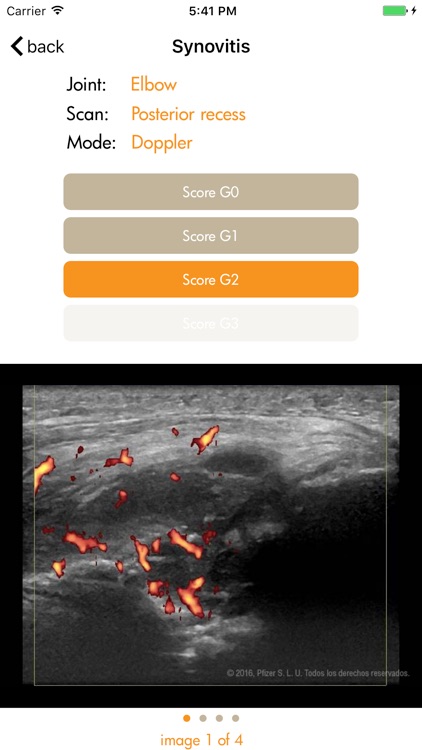

Ultrasound detected synovitis is a powerful imaging tool used worldwide that helps diagnose, monitor and treat patients with rheumatoid arthritis . RAUSSA application has been developed to help you score joint and tendon ultrasound grey scale and Doppler detected synovitis while performing your ultrasound examination. RAUSSA is made-up of almost 400 images from patients with rheumatoid arthritis. Takes no more than 2 minutes to learn! In every area you can look at a representative anatomic specimen image, up to 4 different US images with the same grey scale or Doppler mode score. , Dr. J. Uson MD PhD , Dr. I. Möller MD PhD and Dr. E. Naredo MD PhD, experts in rheumatologic ultrasound have obtained the images in this app.

Ultrasound detected synovitis is a powerful imaging tool used worldwide that helps diagnose, monitor and treat patients with rheumatoid arthritis . RAUSSA application has been developed to help you score joint and tendon ultrasound grey scale and Doppler detected synovitis while performing your ultrasound examination. RAUSSA is made-up of almost 400 images from patients with rheumatoid arthritis. Takes no more than 2 minutes to learn! In every area you can look at a representative anatomic specimen image, up to 4 different US images with the same grey scale or Doppler mode score. , Dr. J. Uson MD PhD , Dr. I. Möller MD PhD and Dr. E. Naredo MD PhD, experts in rheumatologic ultrasound have obtained the images in this app.

The ultrasound definitions and semi-quantitative scoring method used in this app. are those driven and reported by OMERACT (Outcome Measures in Rheumatology in Clinical Trials) validated for diagnoses and monitoring inflammatory activity in patients with rheumatoid arthritis (Bruyn GA, Naredo E, Iagnocco A. J Rheumatol 2015;42 (11):2172-6).